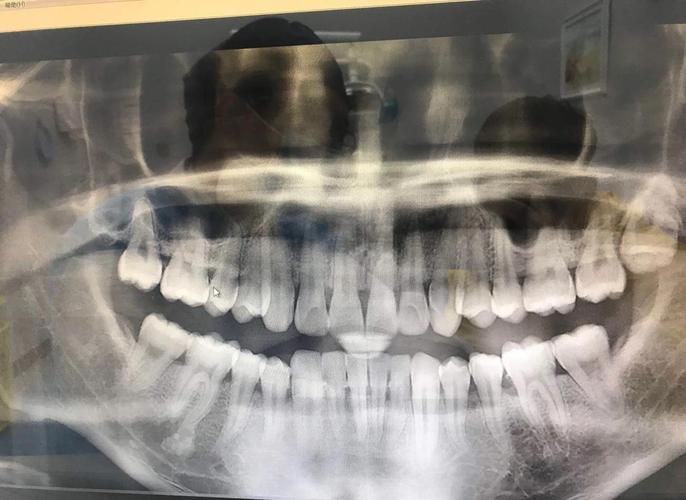

全景片(曲面断层片)是最基础的检查之一,它能一次性显示全口牙齿、牙槽骨、颌骨、上颌窦、下颌神经管等重要结构,通过全景片,医生可以观察牙齿的数量(是否存在多生牙、缺失牙)、位置(牙齿是否萌出正常、有无阻生)、牙根形态(有无弯曲、吸收)、牙槽骨密度及高度(评估牙周支持情况),以及颌骨内是否有囊肿、肿瘤等病变,对于疑似埋伏智齿的患者,全景片能清晰显示智齿的位置、与邻牙及下颌神经管的关系,为拔除方案提供依据,全景片是二维影像,存在重叠伪影,对细微结构的观察有限,因此需要结合其他检查。

| 全景片 | 观察全口牙齿、牙槽骨、颌骨及周围结构,判断牙齿数量、位置、牙根形态 | 常规正畸初筛,评估埋伏牙、多生牙、牙槽骨状况 | 二维影像,存在重叠,需结合其他检查 |